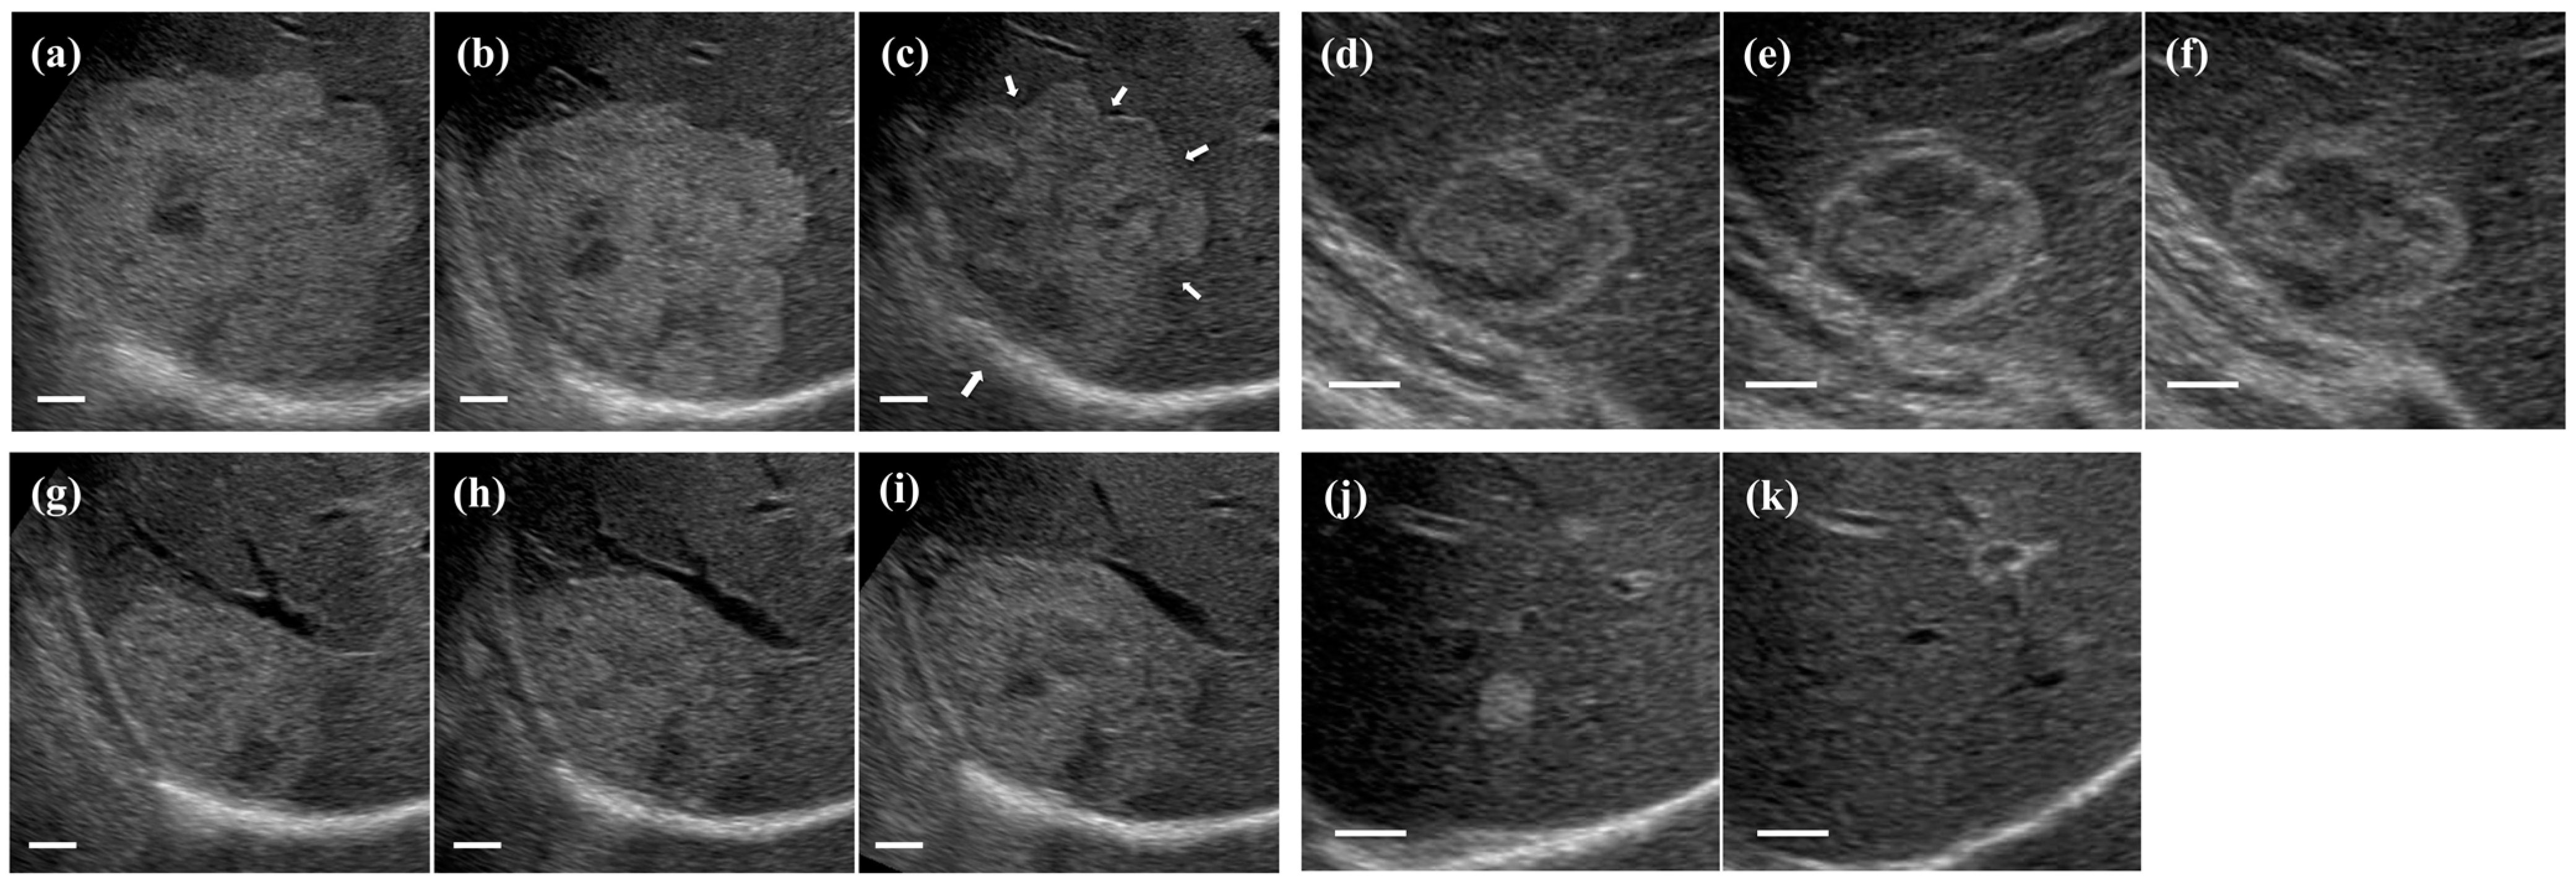

3.3. Ultrasonographic Follow-Up

| Ultrasound findings | ||||

| Echo pattern | <0.0001 | |||

| Homogeneous type (n) | 122 (99.2%) | 27 (42.9%) | 0 (0%) | |

| Mixed type (n) | 1 (0.8%) | 36 (57.1%) | 25 (100%) | |